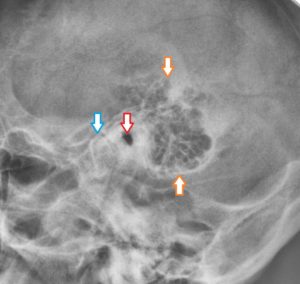

КТ анатомия сосцевидного отростка: особенности и показания